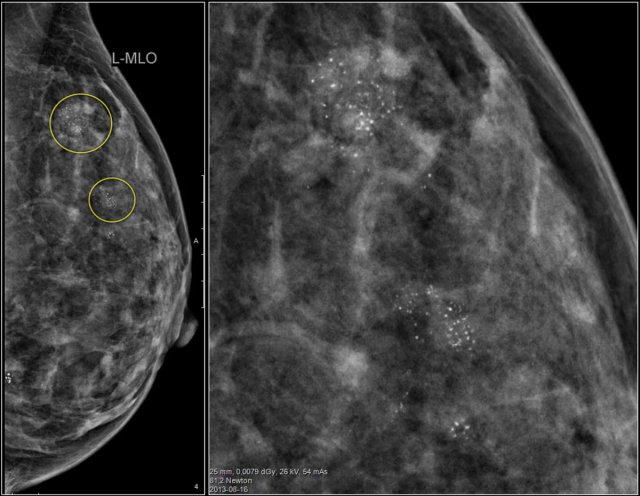

Study the images and describe the calcifications.

Then continue reading.

The findings are:

- Morphology: some are coarse heterogenous and some look more like fine pleomorphic.

- Distribution: Some calcifications are in a group ( <2cm) and some are in a regional distribution ( >2cm), but not in a segmental or linear arrangement.

This proved to be multifocal DCIS with areas of invasive carcinoma.